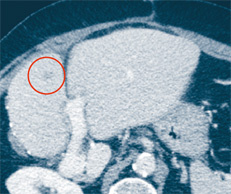

Abb. 2b

Im Rahmen des thermoablativen Verfahrens wird eine Sonde exakt ins Zentrum der Metastase vorgeschoben, und der Tumor wird anschliessend «verkocht».

Die thermoablativen Verfahren, beispielsweise Radiofrequenzablation oder Mikrowelle (Abb. 2b), werden vor allem zur Behandlung von Tumoren in Leber und Niere, aber auch am Knochen angewandt. CT-gesteuert werden spezielle Ablationsnadeln gezielt ins Tumorgewebe eingebracht, um dieses durch grosse Hitze vollständig zu zerstören. Abhängig von der Tumorgrösse ist der Therapieerfolg einer AblationAblation: Entfernen von Körpergewebe mit dem einer Operation vergleichbar.